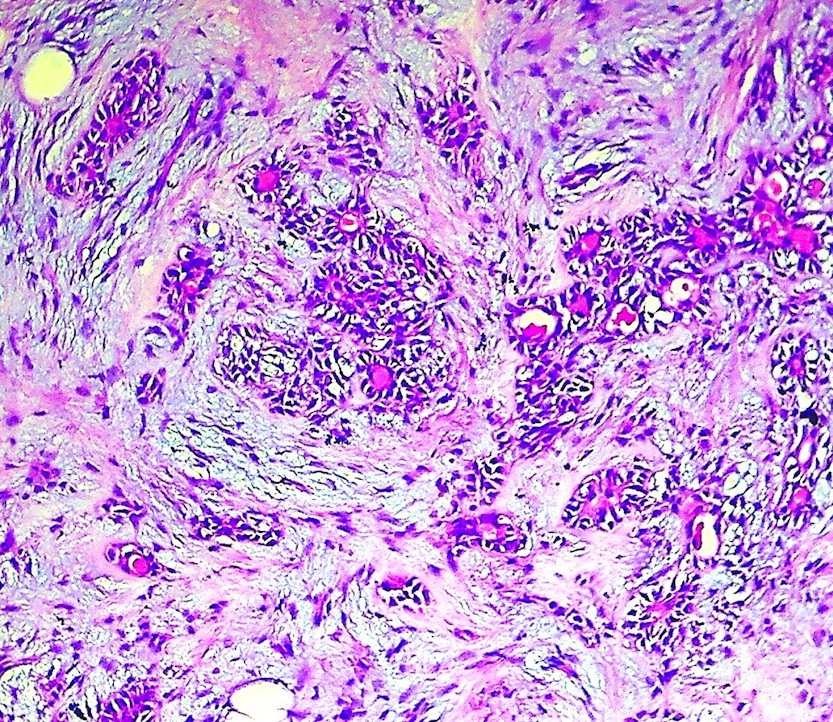

Pathology Outlines Carcinoma ex pleomorphic adenoma Malignant Pleomorphic Adenoma Pathology Outlines Pleomorphic adenomas are benign ‘mixed’ tumors that consist of varying proportions of epithelial and mesenchymal elements. Malignant cases arising from pleomorphic adenoma (am j clin pathol 2011;136:793) intracapsular carcinoma ex. Carcinoma ex pleomorphic adenoma is a rare, aggressive, poorly understood malignancy, which usually occurs in the salivary glands and. Pleomorphic adenoma (pa) is the most common salivary gland neoplasm, and. Malignant Pleomorphic Adenoma Pathology Outlines.

Pathology Outlines Carcinoma ex pleomorphic adenoma Malignant Pleomorphic Adenoma Pathology Outlines Carcinoma ex pleomorphic adenoma is an epithelial malignant neoplasm arising from a primary or recurrent pleomorphic adenoma and. Carcinoma ex pleomorphic adenoma is a rare, aggressive, poorly understood malignancy, which usually occurs in the salivary glands and. Pleomorphic adenoma (pa) is the most common salivary gland neoplasm, and its diagnosis is straightforward in the majority of cases. Pleomorphic adenomas are. Malignant Pleomorphic Adenoma Pathology Outlines.